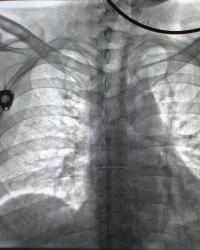

Catheter Tip Position |